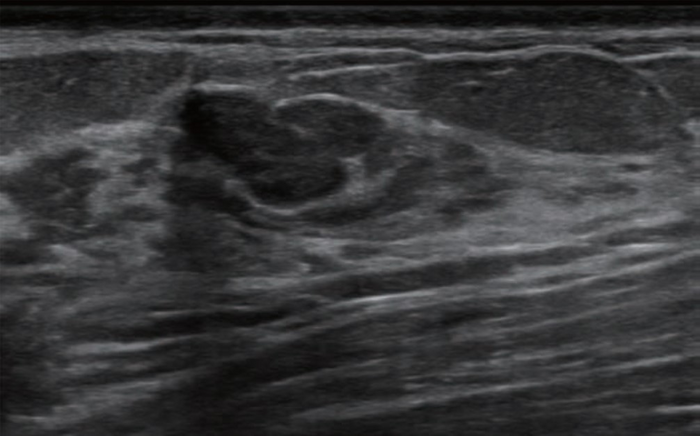

Leesburg, VA, May 17, 2023 According to an accepted manuscript published in ARRS’ own American Journal of Roentgenology ( AJR ) , deep learning–based computer-aided diagnosis (CAD) for breast lesion classification on ultrasound significantly improved radiologists’ diagnostic performance—particularly for reducing the frequency of benign breast biopsies.

Cui et al.’s AJR study included patients scheduled to undergo biopsy or surgical resection of a breast lesion, classified as BI-RADS category 3-5 on prior breast ultrasound, at eight Chinese secondary or rural hospitals from November 2021 to September 2022. Patients underwent an additional investigational breast ultrasound, both performed and interpreted by a radiologist with no expertise in the modality. Hybrid body-breast imagers—radiologists lacking breast subspecialty training or in whom breast ultrasound accounted for less than 10% of their ultrasounds performed annually—then assigned a BI-RADS category. CAD results were used to upgrade reader-assigned BI-RADS category 3 lesions to category 4A, as well as for downgrading BI-RADS 4A lesions to 3. Histologic results of biopsy or resection served as the researchers’ reference standard.

Ultimately, application of CAD to interpretations by radiologists without breast ultrasound expertise resulted in upgrade of 6.0% (6/100) of BI-RADS category 3 assessments to category 4A, of which 16.7% (1/6) were malignant, and downgrade of 79.1% (87/110) of category 4A assessments to category 3, of which 4.6% (4/87) were malignant.